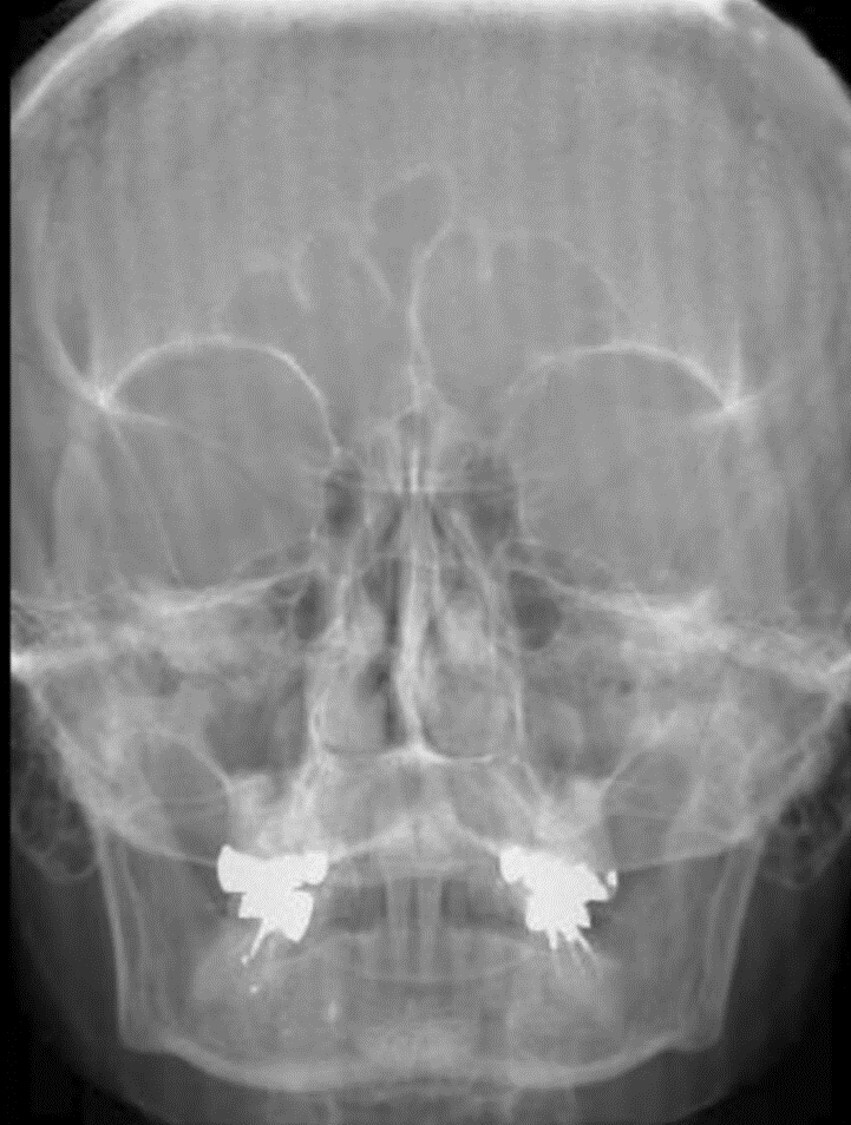

13

Q

Aside from the surgically implanted hardware, what artifact is seen in the attached image?

A

Quantum mottle from underexposure